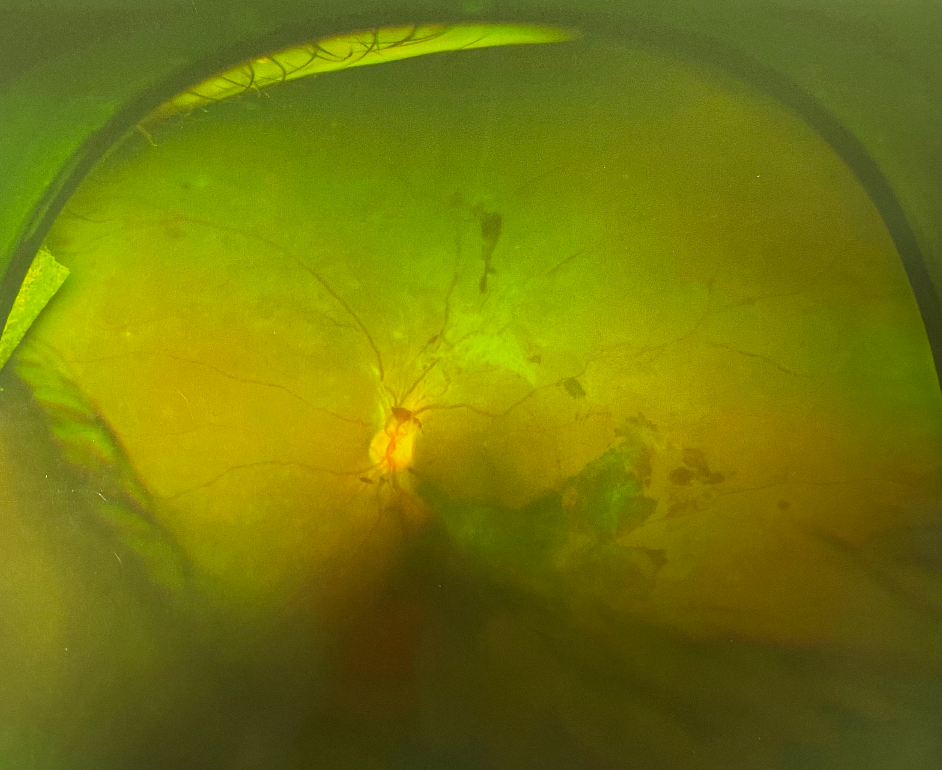

眼底出血并不是一種獨(dú)立的眼病,且出血的原因復(fù)雜,對(duì)視力的影響也很大。如果不及時(shí)加以改善和控制,還有可能引起黃斑病變、青光眼等許多嚴(yán)重并發(fā)癥,甚至是失明。很多人沒有出現(xiàn)眼底出血的情況,因而對(duì)其不甚了解。那么眼睛眼底出血原因有哪些?今天就和大家一起了解下眼睛眼底出血原因。

老年性黃斑變性引起的眼底出血部位一般限于黃斑變性,好發(fā)于50歲以上的老年人。主要表現(xiàn)為突然視力下降,到了病情晚期,還會(huì)出現(xiàn)大面積視網(wǎng)膜下出血、玻璃體出血,對(duì)視力的損傷極大

如果患者有高血壓、動(dòng)脈硬化的病史,在出現(xiàn)視網(wǎng)膜靜脈分支堵塞時(shí)就有可能出現(xiàn)視力突然下降、視網(wǎng)膜水腫和滲出。若是視網(wǎng)膜指定脈堵塞或視網(wǎng)膜中央靜脈堵塞,患者在眼底出血的同時(shí)還可能伴有明顯的視力下降

當(dāng)糖尿病患者發(fā)生時(shí)視網(wǎng)膜病時(shí)便會(huì)出現(xiàn)眼底出血。在病癥初期,大都表現(xiàn)為少量點(diǎn)狀出血,并伴有微血管瘤。隨著病情的發(fā)展,患者的眼睛可能會(huì)有點(diǎn)狀的出血和滲出,有的患者還會(huì)有黃斑病變及視力下降的癥狀。因此糖尿病患者一定要按時(shí)按量的服用藥物,只有將糖尿病的癥狀控制了才能有效控制眼底出血這一情況。

除了上述的這三種病癥,炎癥性疾病、免疫復(fù)合物侵犯血管壁時(shí)、全身性血管病和血液病分也可引起高血壓視網(wǎng)膜病變和糖尿病性視網(wǎng)膜病變,從而導(dǎo)致眼底出血,比如高血壓視盤血管炎等。